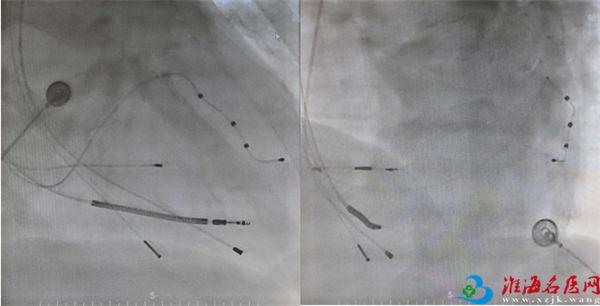

患者闫某,男,89岁,因“反复活动后胸闷憋喘5年余”于徐州市中医院心血管内科就诊。十年前,闫某曾因房颤伴长间歇于徐州市中医院行单腔起搏器置入术。近五年,闫某出现活动后胸闷憋喘,多次于徐州市中医院住院治疗。心血管内科的专家们对闫某进行规范化药物治疗后,其心脏彩超EF值仍逐年下降。一月前,闫某再次因活动后胸闷憋喘至徐州市中医院就诊。心脏彩超提示EF32%,起搏器程控提示心室起搏比例71%。在与闫某及家属充分沟通病情后,心血管内科专家决定为闫某行左束支区域起搏优化的心脏再同步化治疗(LBBP-Optimized CRT,LOT-CRT)。术后,闫某恢复良好,活动后胸闷憋喘改善明显。LOT-CRT的成功植入标志着徐州市中医院在起搏电生理方面的技术水平更进一步,紧跟国内的先进技术步伐。

答:心脏再同步化治疗(CRT)是治疗心衰的一项重要的手段,LOT-CRT是结合传统心脏再同步化左室起搏与左束支区域生理性起搏的一种最优化改善心脏功能的起搏方式。在左束支起搏后,进行左室心外膜电极起搏优化。大部分患者单纯左束支区域起搏就能纠正左束支传导阻滞,从而达到生理性的心脏再同步化效果。LOT-CRT术式理论上可进一步纠正心室收缩不同步,以提高CRT反应率,提高患者的生存质量和延长生存期。